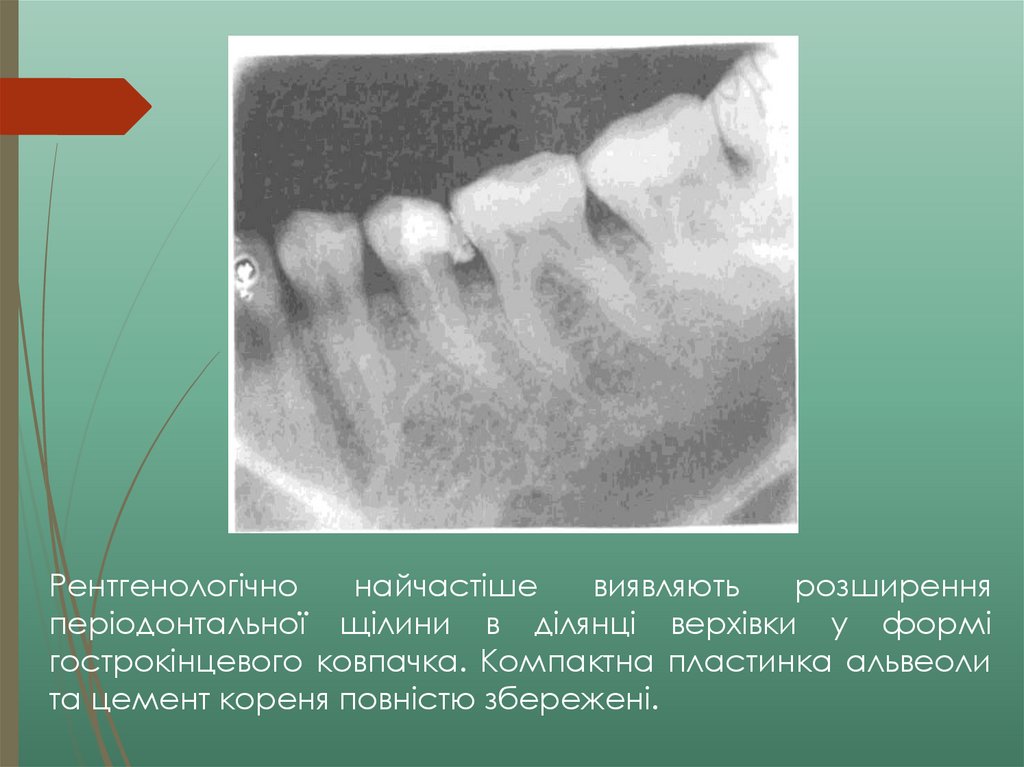

2.44M

1. Вінницький національний медичний університет ім. М. І. Пирогова

Клініка, діагностика, диференціальна

діагностика гострих, хронічних форм та